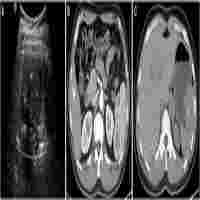

| Abstract | Background Sclerosing angiomatoid nodular transformation is a benign disorder of splenic tissue and is often mistaken as a potentially malignant entity in the diagnostic process. To the best of our knowledge, this is the first report of sclerosing angiomatoid nodular transformation mimicking metastasis of melanoma in the literature. Case presentation A 43-year-old white man presented with a newly found splenic mass 4 years ago to our Department of Gastroenterology. He was diagnosed as having a superficial spreading malignant melanoma localized at his left instep 7 years ago and was successfully treated with radical local resection. Several diagnostic procedures were conducted. Ultrasound showed a hypoechoic lesion in the inferior pole of his spleen with a diameter of 2 cm, blurred boundaries, and inhomogeneous interior pattern. Contrast-enhanced ultrasound was inconclusive and showed only discrete contrast enhancement of the lesion with accentuated nodule-like enrichment of the boundaries in the arterial phase. Computed tomography and magnetic resonance imaging scans showed two splenic lesions which were highly suspicious of metastasis. Magnetic resonance imaging of his head was inconspicuous. Bone scintigraphy showed no abnormal results. Fine-needle aspiration indicated metastasis of the above-mentioned malignant melanoma. We conducted a laparoscopic splenectomy. His intraoperative and postoperative course were uneventful. In contrast to the result of the fine-needle aspiration, the presence of metastasis of melanoma could not be confirmed. Histological analysis revealed nodule-like arrangement of fibroblasts with low cell density and a predominance of dilated capillaries, indicating sclerosing angiomatoid nodular transformation of the spleen. Conclusions There are no preoperative diagnostic imaging procedures which can definitely differentiate sclerosing angiomatoid nodular transformation from malignancies in cases of morphological and immunophenotypic variations of the specimen. Morphological and immunophenotypic variations of the specimen represent a diagnostic challenge and can mimic malignoma. As reported in our case, the specimen obtained by ultrasound-guided fine-needle aspiration led to the diagnosis of metastasis of melanoma. Splenectomy is often conducted due to a splenic mass suspicious of malignoma as described in our case or with unknown valency in different diagnostic imaging procedures. |